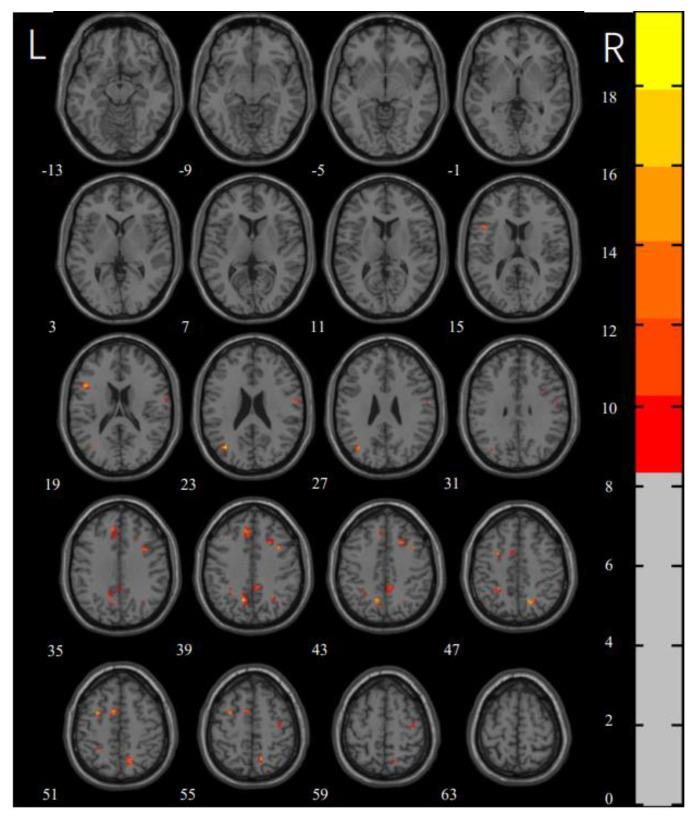

Extensive abnormalities in spontaneous brain activity involving frontal, temporal, and occipital regions were observed in the patients compared to the HCs. The differences in local brain functioning between checking and washing OCD were mainly concentrated in the bilateral middle frontal gyrus, right supramarginal gyrus, right angular gyrus, and right inferior occipital gyrus. The ROC curve analysis revealed that the hyperactivation right middle frontal gyrus had a better discriminatory value for checking and washing OCD. Furthermore, the seed-based FC analysis revealed higher FC between the left medial superior frontal gyrus and right caudate nucleus compared to that in the healthy controls.

These findings suggest that extensive local differences exist in intrinsic spontaneous activity among the checking group, washing group, and HCs. The neural basis of checking OCD may be related to dysfunction in the frontal-striatal network, which distinguishes OCD from washing OCD.

与HCs相比,患者在额叶、颞叶和枕叶区域的自发脑活动存在广泛异常。检查型和洗涤型强迫症之间局部脑功能的差异主要集中在双侧额中回、右侧缘上回、右侧角回和右侧枕下回。ROC曲线分析显示,右侧额中回的过度激活对检查型和洗涤型强迫症具有更好的鉴别价值。此外,基于种子点的FC分析显示,与健康对照相比,左侧额上内侧回与右侧尾状核之间的FC更高。

这些发现表明,检查组、洗涤组和HCs之间在内在自发活动方面存在广泛的局部差异。检查型强迫症的神经基础可能与额叶-纹状体网络功能障碍有关,这将其与洗涤型强迫症区分开来。